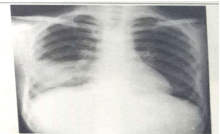

試題1:男性,26歲,受涼后寒顫高熱,咳嗽,咳鐵銹色痰5天(2分)

A.肺癌

B.氣胸

C.正常胸片

D.肺炎

E.胸腔積液

答案:D

影像學(xué)1